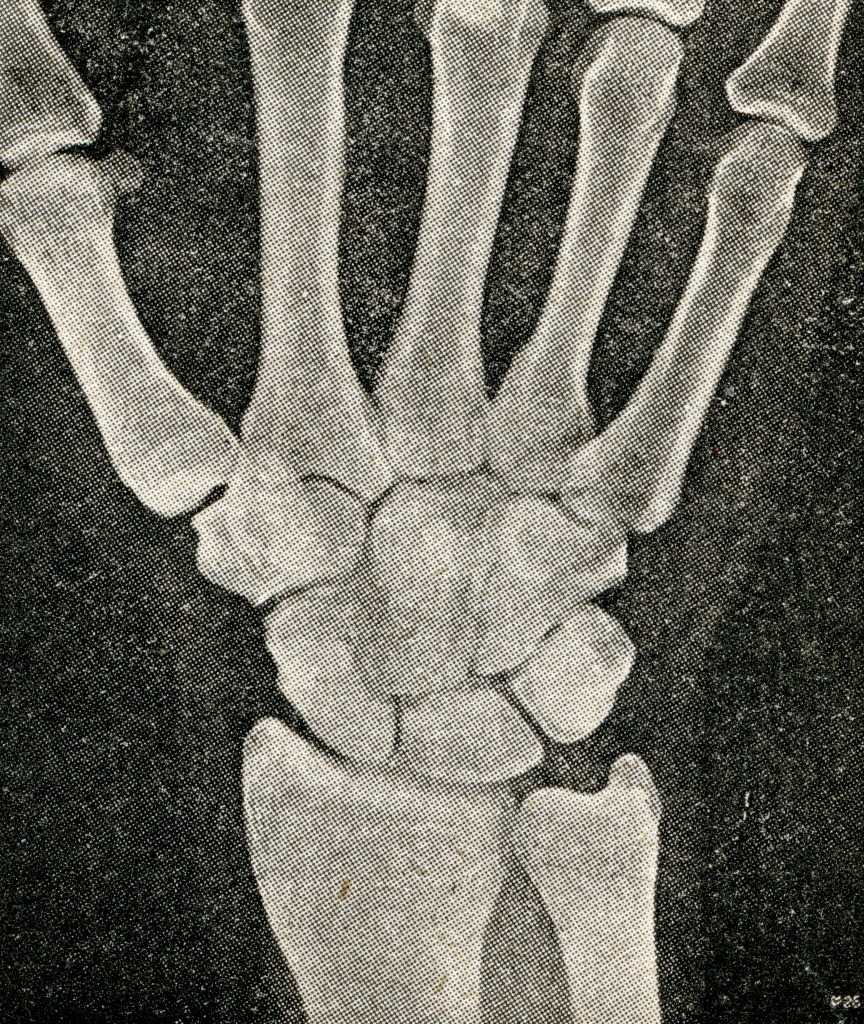

Es ist der 8. November 1895, an dem Wilhelm Conrad seiner täglichen Arbeit nachgeht. Bis zu diesem Datum hat er sich mit den Eigenschaften des Quarzes und der Verdichtbarkeit von Flüssigkeiten beschäftigt. Er untersucht die elektrische Leitfähigkeit von Gasen bzw. deren Eigenschaften, als er eine unsichtbare Strahlung entdeckt. Die Strahlung, mit der man das verborgene Innere von Organismen sichtbar machen kann, nennt er „X-Strahlen“ – später wird sie nach ihm als „Röntgenstrahlung“ benannt.

Er berichtet persönlich Kaiser Wilhelm und im Januar 1896 wird die erste Abbildung eines Röntgenbildes veröffentlicht. Wie so oft, wird die neue Technologie eingesetzt, ohne sich über die Wirkung im „Guten“ wie im „Bösen“ intensiv schlau zu machen. Und so bleibt es nicht aus, dass der Einsatz und das Experimentieren, einigen Pionieren das Leben kostet. Röntgen selbst bestrahlt z.B. die Hand von Marie Kundt 20 Minuten.